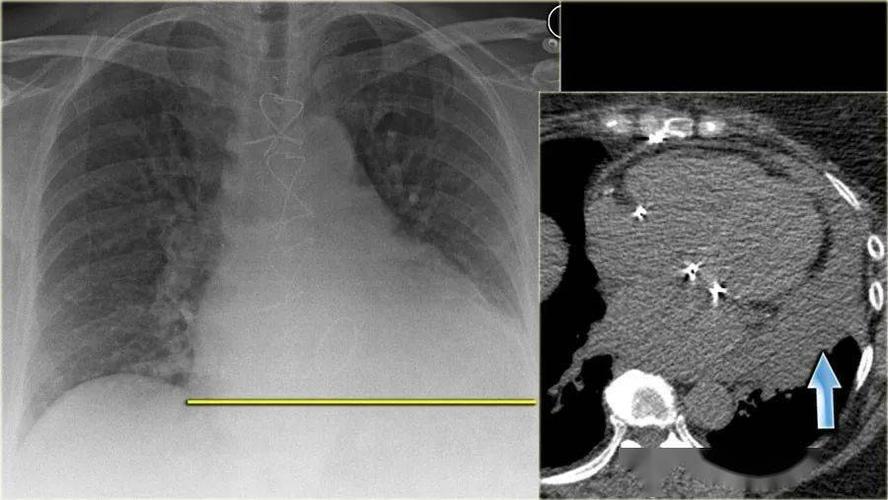

胸片心力衰竭

请大家分析一下左侧胃泡区液平,该片存在哪些问题. 2.